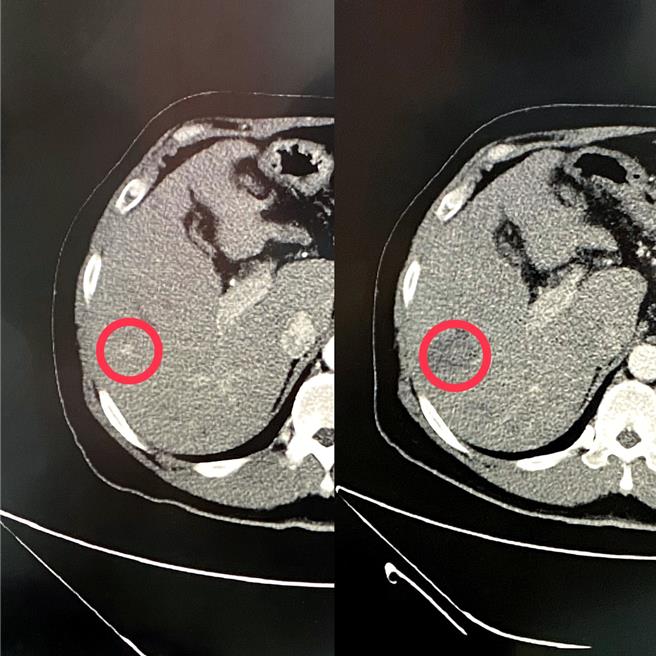

透过电脑断层扫描可见病患术前有0.5公分肿瘤(左图),给予微创射频消融术治疗后肿瘤已消失(右图)。(图/台中荣总)

57岁许姓职业驾驶因患有慢性B型肝炎及肝癌病史,8年前曾接受手术治疗,追踪检查发现肝臟肿瘤指数逐渐上升,一度飙升至正常值的40倍,经安排电脑断层检查后,发现有0.5公分復发肝癌,进行射频消融术治疗后,至今未发现肿瘤復发。